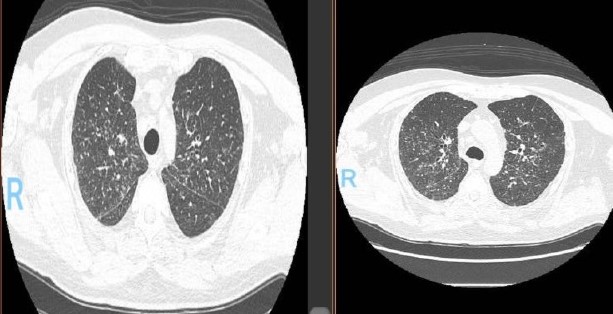

En la tomografía computada de tórax en ventana pulmonar se identifica un patrón micronodular con distribución perilinfática y difusa en ambos hemitórax. Este hallazgo se acompaña de un engrosamiento peribronquial notable, así como de opacidades en vidrio deslustrado, que predominan en las zonas subpleurales y en las regiones posteriores de ambos pulmones.

En la tomografía computada de tórax en ventana mediastínica se observan múltiples adenopatías localizadas en diversas áreas del cuello y mediastino. Estas adenopatías se distribuyen en las cadenas yúgulo-carotídeas, en ambas regiones supraclaviculares y a lo largo del mediastino, abarcando específicamente las siguientes áreas: la región paratraqueal superior derecha, los espacios retrocavo-pretraqueal y prevascular, la zona subcarinal, la ventana aortopulmonar y en la región de la arteria mamaria (AM). La presencia de estas adenopatías sugiere un compromiso linfático difuso en estas zonas.